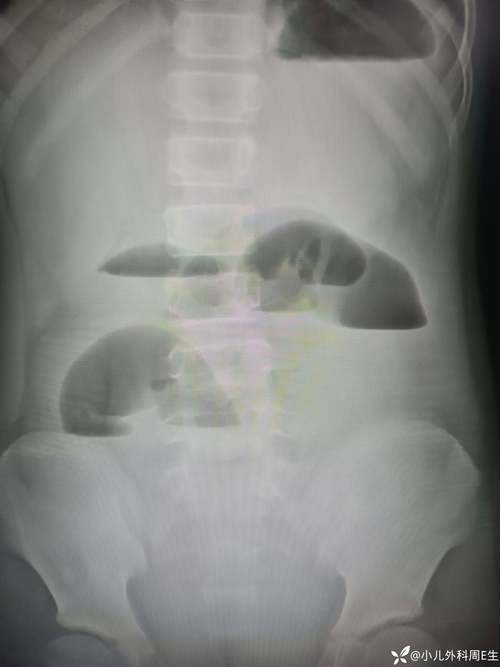

X线检查:看肠管胀气和液平面